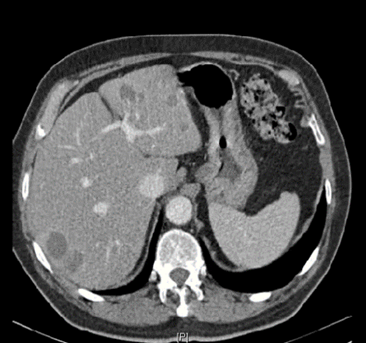

Vad visar bilden?

• Levermetastaser inringat

• Ljusa stråk är levervener